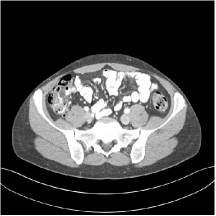

III.C.2. Simulation Framework, Reconstruction Results, and Comparisons

The synthesized low-dose clinical measurements are simulated from regular-dose images at a resolution of mm with a fan-beam CT geometry corresponding to a monoenergetic source at incident photon intensity . The sinograms are of size . The width of each detector column is mm, the source to detector distance is mm, and the source to rotation center distance is mm. We reconstruct images of size with the pixel size being mm mm.

We conducted experiments on one test slice used for parameter tuning (L067-slice 120) and four independent test slices (L109-slice 90, L192-slice90, L333-slice140, L506-slice 100) of the Mayo Clinic data. For PWLS-EP, we ran iterations using relaxed OS-LALM and set regularization parameter . We used the same as the phantom experiments for Algorithm 2. The process of selecting a general set of reconstruction parameters () for the Mayo Clinic test slices is identical to that for the XCAT phantom in Section III.B.2. The selected regularization parameter and the parameters that control the sparsity of the coefficient maps are for ST, , , , , for MARS2, , , , , , , for MARS3, , , , , , , , , , , for MARS5, and , , , , , , , , , , , , , , for MARS7, respectively.

Figs. 8, 9, 10, and 11 show the reconstructions of the four independent slices using the FBP, PWLS-EP, PWLS-ST, PWLS-MARS2, PWLS-MARS3, PWLS-MARS5, and PWLS-MARS7 schemes, respectively. Additional Mayo Clinic experimental results of the parameter tuning case (Fig. 15) are shown in the supplementary document. Table 1 lists the RMSE and SSIM values of reconstructions of the four independent test slices, with the best values bolded. Generally, the five and seven layer models provided the best RMSE and SSIM values. They outperform the single-layer model by HU in RMSE on average. However, the MARS5 and MARS7 models perform similarly. In order to strengthen the benefits of the multi-layer model, Table 2 lists the RMSE of the reconstructions in four different ROIs (shown in the reference of Fig. 11) with seven methods for slice 100 of patient L506. By observing the reconstructed images, we see that although the ST model achieves a cleaner reconstruction result than FBP and PWLS-EP, it still sacrifices some sharpness of the central region and suffers from loss of details. The deeper models have a somewhat more positive effect in terms of maintaining subtle features, which is clearly more essential to clinical diagnosis. Furthermore, as we will discuss later, after considerable parameter tuning, we found that the information contained in residual maps is gradually decreased with the number of layers, eventually vanishing at some layer, which suggests that very deep unsupervised models might not offer significantly better image quality.